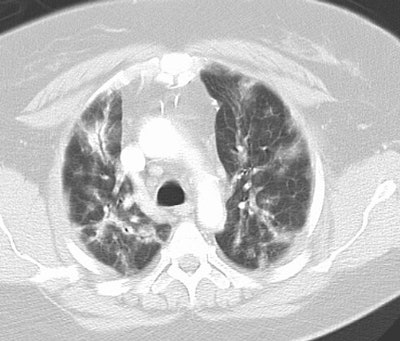

Cryptogenic Organizing Pneumonia (BOOP):

The patient shown below had a long history of inflammatory bowel disease for which she was receiving treatment with sulfasalazine. This agent can result in BOOP.

The CT scan demonstrates subpleural, patchy consolidations with air bronchograms. Patchy areas of ground-glass are also seen. Peribronchial thickening as shown in this case is a common finding.